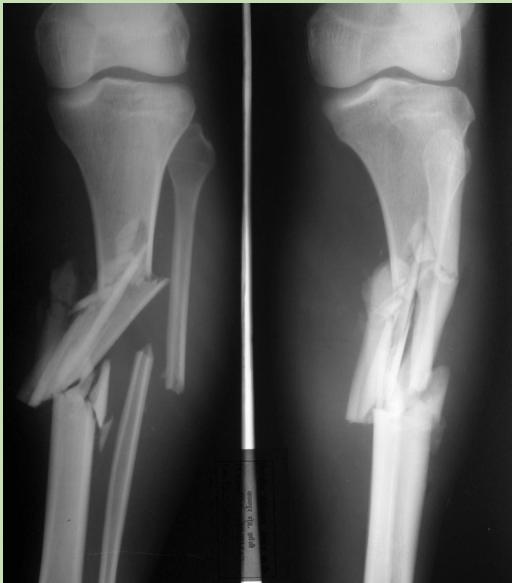

Case Scenario 1: Open Tibia Fracture

Patient Presentation:

- A 30-year-old man was involved in a car accident

- Brought to the emergency room unconscious

- Large wound at the anterior aspect of left leg with severe deformity and bone exposed